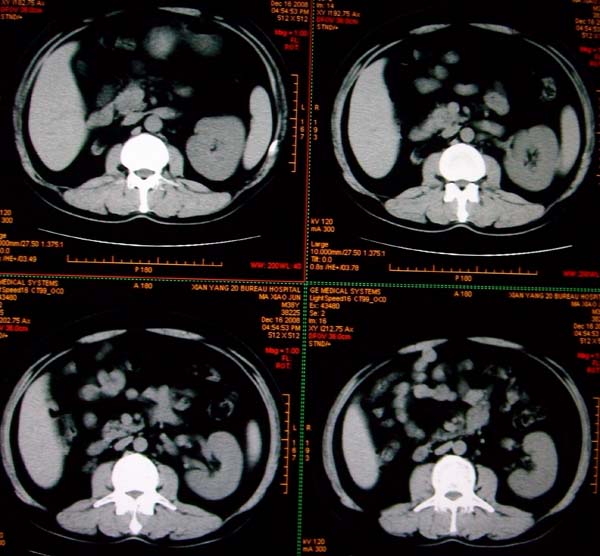

标题: CT17174:M38Y,体检超声提示右肾发育不良,病人无明显不适 [打印本页]

标题: CT17174:M38Y,体检超声提示右肾发育不良,病人无明显不适

右肾发育不良;考虑左肾下极血管平滑肌脂肪瘤可能,建议增强。

右肾微小发育不良  左肾下极错构可能

1)左肾下极占位性病变,不排除肾癌可能;建议行进一步检查。2)右肾发育不良。

左肾下极占位性病变,不排除肾癌可能;建议增强及明确内部组织ct值。右肾发育不良。

右肾发育不良。左肾下极占位。

右肾发育不良。左肾代偿。左肾下极占位,性质待定,建议强化。

右肾发育不良

右肾发育不良。左肾下极占位。建议增强!

右肾发育不良。左肾下极占位。  强化

右肾发育不良。左肾下极囊实性占位,建议增强。